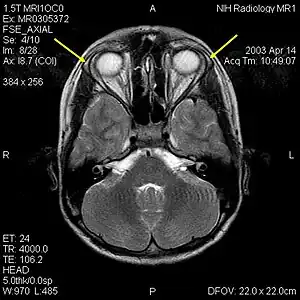

| MRI of the brain of 12-year-old boy with triple-A syndrome showing hypoplastic lacrimal glands (yellow arrows.) | |